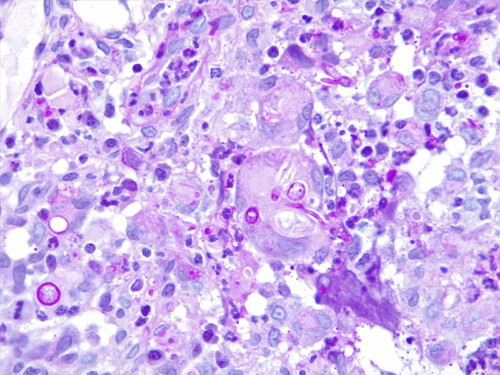

Cette dernière est négative mais l’analyse histopathologique, examinée en coloration standard et APS, montre des lésions nodulaires, isolées ou parfois coalescentes siégeant dans le derme et s’étendant jusque dans l’hypoderme, formées d’une plage dense de cellules macrophagiques dont le cytoplasme apparaît granuleux, basophile. Ces foyers granulomateux sont centrés par plusieurs éléments basophiles constitués d’un cément bleuté, parsemé d’éléments fongiques, ovoïdes, mais également filamenteux, réfringents. Aucun élément fongique n’est mis en évidence au sein des annexes cutanées, mais certains granulomes sont en rapport ou à proximité directe de follicules pileux (photos 5 et 6).

Photos 5 et 6 : aspect histopathologique des lésions : notez la présence de lésions nodulaires, isolées ou parfois coalescentes siégeant dans le derme et s’étendant jusque dans l’hypoderme (photo 5) et de foyers granulomateux centrés par des éléments fongiques, ovoïdes et filamenteux ramifiés (hyphes) (photo 6).